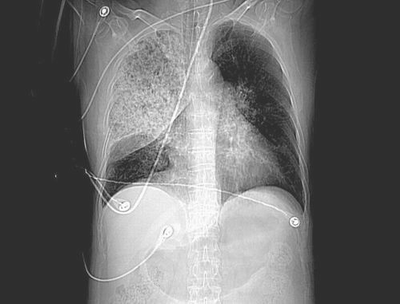

患者,男,60岁,病史如下:

2008.8.17ct定位片

病变从8.11-8.17明显改变,增多,以蜂窝状改变为主,类蜂窝肺,似弥漫性肺泡癌,但是病变进展太快,不符合弥漫性细支气管肺泡癌。因此考虑为特殊微生物感染,多以霉菌类常见,建议细菌微生物学检查。

疑点二:影象表现怪异,大片阴影内见多发筛孔征,如何解释.